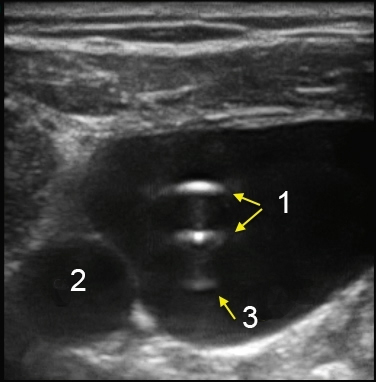

M-Turbo:IJV短軸のカテーテル画像

カテーテル

内頚動脈

アーチファクト